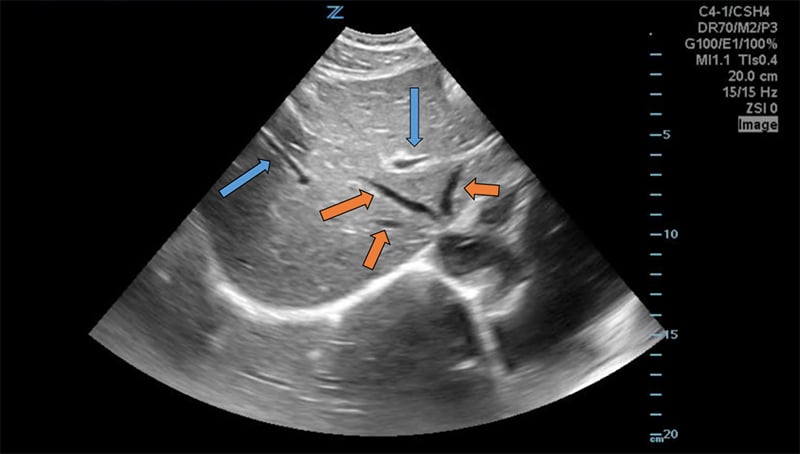

Figure 8. Transverse subxiphoid view of the liver. Hepatic veins (orange arrows) are straight with thin walls, whereas portal veins (blue arrows) have bright walls and are more tortuous.